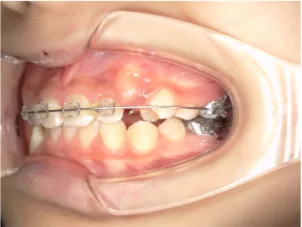

治療中③中1:非抜歯治療の診断で、上顎に歯の生えるスペースをつくるため上顎左右6をプレートで遠心移動し、隙間ができた時点

マルチブラケット法へ移行します

| 行ったご提案・診断内容 | 生え変わりが終わってなくマルチブラケット法による咬合治療には早い時期のため、顔立ちの成長を促す目的で歯列弓(アーチ)の拡大と前歯を並べながら永久歯が生えるのを待ち、咬合治療開始時に再診断で抜歯、非抜歯を最終検討する提案をしました。 再診断時(写真②)、歯列の拡大と上顎前歯の並べ替えはされていましたが八重歯となったため抜歯、非抜歯を検討しました。 口元は特に問題がなく非抜歯で八重歯を改善するためのスペースを作ることが可能なため非抜歯治療を提案しました。 治療は、 ・拡大および上顎左右6を遠心移動させてスペースを作る 予定装置 |